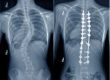

Veja o exemplo de uma Endoscopia de Coluna: